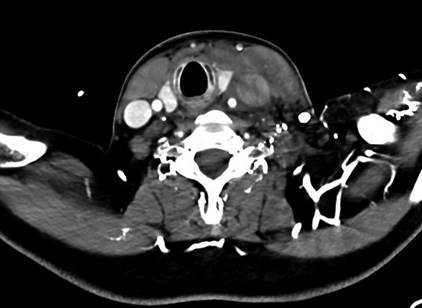

The patient underwent a computed tomography (CT) scan

that reported thrombosis of the left internal jugular vein, with occlusion of

the left brachiocephalic and subclavian veins (shown

in Fig.

1). There was no

evidence of collections/abscesses. A brief transthoracic echocardiography was

Fig.

1. CT scan – axial plane. Carinal shift

due to jugular vein thrombosis and ipsilateral edema.